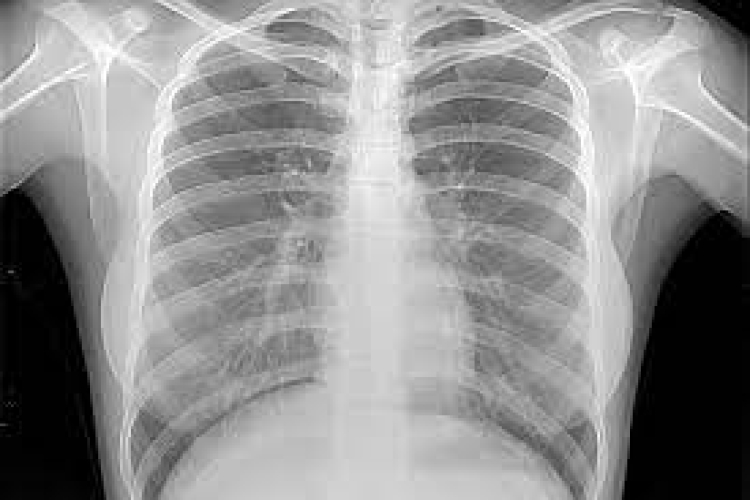

К общим симптомам ХОБЛ относятся одышка, хронический кашель, часто с мокротой, утомляемость. По мере прогрессирования хронической обструктивной болезни легких людям становится все труднее выполнять обычную повседневную деятельность, часто из-за нехватки воздуха. Они часто страдают от сопутствующих заболеваний, таких как болезни сердца, остеопороз, патологии опорно-двигательного аппарата, рак легких, депрессия и тревожность.

Ежегодно ХОБЛ является причиной смерти около трех миллионов человек. По оценкам специалистов, это число может увеличиться в связи со старением населения планеты и продолжающимся воздействием факторов риска.